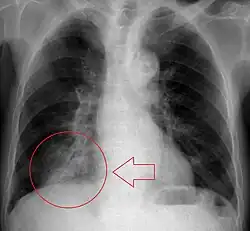

Radiologic studies may be done to image the chest wall, lungs, and airway to evaluate and diagnose conditions that may be contributing to aspiration, and also to diagnose complications of previous aspiration.

Chest X-rays can be useful in the diagnosis of aspiration pneumonia but may be negative early in the course.[12] Chest CT Scan can identify the presence of a pneumonia as well, and can also assist in characterizing abscesses, foreign objects, or pleural disease.